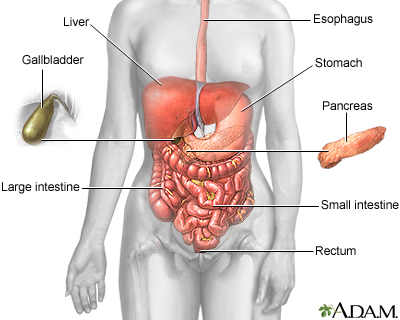

Gallstones are hard deposits that form inside the gallbladder. These may be as small as a grain of sand or as large as a golf ball.

The cause of gallstones varies. There are two main types of gallstones:

- Stones made of cholesterol -- This is the most common type. Cholesterol gallstones are not related to the cholesterol level in the blood. In most cases, they are not visible on CT scans but are visible on a sonogram (ultrasound) of the abdomen.

- Stones made of bilirubin -- These are called pigment stones. They occur when there is too much bilirubin in the bile, often due to too many red blood cells being destroyed.

Blockage by gallstones may cause swelling or infection in the:

- Gallbladder (cholecystitis)

- Tube that carries bile from the liver to the gallbladder and intestines (cholangitis)

- Pancreas (pancreatitis)